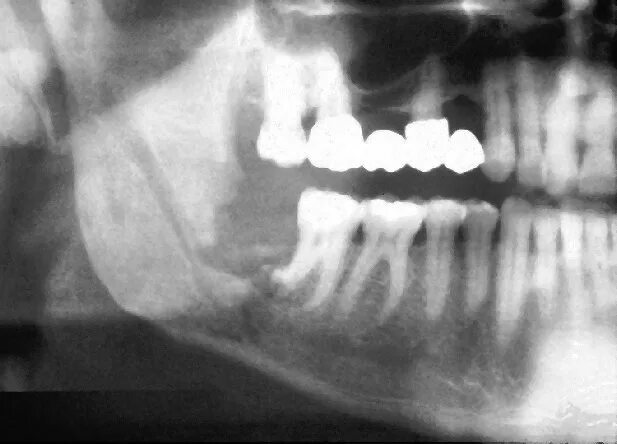

Одонтогенный остеомиелит челюсти. остеомиелит верх челюсти. хронический остеомиелит челюсти снимок. одонтогенного остеомиелита челюстей.

Одонтогенного остеомиелита. одонтогенный остеомиелит нижнечелюстной. остеомиелит верхней челюсти кт. острый остеомиелит верхней челюсти.

Подострая одонтогенного остеомиелита.. одонтогенный остеомиелит рентген. остеомиелит челюсти рентген. одонтогенный остеомиелит челюсти рентген.

Одонтогенный остеомиелит рентген. хронический остеомиелит челюсти. клиника острого остеомиелита нижней челюсти. муфтообразный инфильтрат.